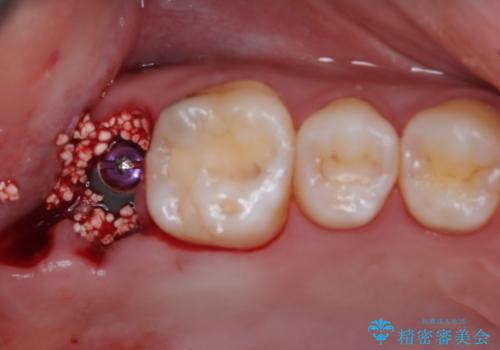

右上のインプラント治療は、1DAYインプラント治療(抜歯即時埋入・即時荷重)の適応となりましたので、通常3回必要な外科処置の回数を1回に集約させることができました。